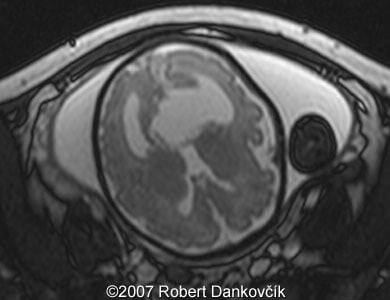

Images 8, 9: MRI; 32 week of pregnancy; transverse sections through the fetal skull showing dilated lateral ventricles and dominant interhemispheric cyst extending to the right.

Images 10, 11: MRI; 32 week of pregnancy; transverse (image 11, left) and parasagittal (image 12, right) sections through the fetal skull showing dilated lateral ventricles and interhemispheric cyst.